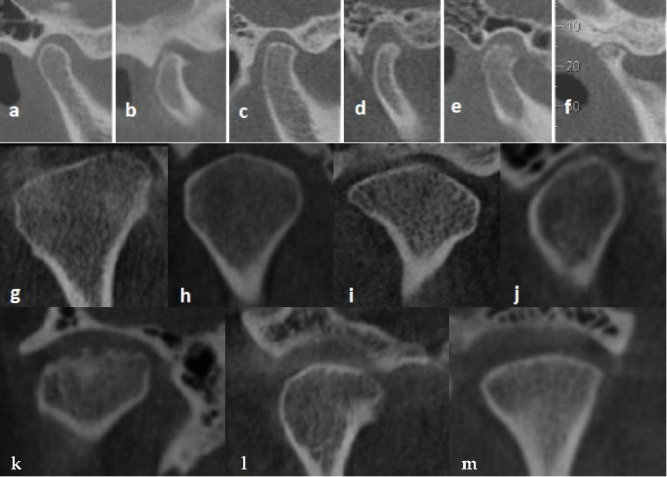

颞下颌关节(TMJ)疾病包括影响关节及其周围结构的各种疾病,通常导致疼痛、功能障碍和结构改变。了解髁突改变的预测因素对于早期诊断和有效治疗至关重要,特别是在有明显功能限制的患者中。目的:本研究旨在通过锥形束计算机断层扫描(CBCT)检测性别和皮质分类对下颌髁突变化的综合影响,以确定TMJ退变的关键预测因素。方法:对64例30岁及以上行CBCT成像的患者(男33例,女31例)进行横断面研究。分析人口统计学数据(年龄、性别)、牙齿因素(剩余牙齿数、后牙缺失)和解剖学测量(髁突高度、宽度、长度和下颌髁上的皮质[CMC])。髁突改变分为骨赘、变平、硬化、侵蚀或假性囊肿。采用卡方检验、独立t检验和逻辑回归来确定髁突变化的预测因素。结果:女性出现髁突变化的可能性明显高于男性,比值比(OR)为0.18,表明男性出现这些变化的可能性要低82%。CMC分类也发挥了重要作用;CMC等级为0或1的个体发生髁突改变的风险是CMC等级为2的个体的7.5倍。此外,髁突高度降低与退行性变显著相关(受影响个体的平均高度为20.49±2.5 mm,未受影响个体的平均高度为22.34±3.2 mm, p=0.017)。结论:性别和CMC分型是TMJ障碍患者髁突变化的重要预测因素。

Introduction: Temporomandibular joint (TMJ) disorders encompass a wide range of conditions impacting the joint and its surrounding structures, often leading to pain, dysfunction, and structural alterations. Understanding the predictors of condylar changes is crucial for early diagnosis and effective management, particularly in patients experiencing significant functional limitations. Objectives: This study aimed to examine the combined impact of sex and cortication classification on mandibular condylar changes, as detected by cone-beam computed tomography (CBCT), to identify key predictors for TMJ degeneration. Methods: A cross-sectional study was conducted on 64 patients (33 men, 31 women) aged 30 years and older, who underwent CBCT imaging. Demographic data (age, sex), dental factors (remaining teeth count, posterior tooth loss), and anatomical measurements (condylar height, width, length, and cortication on the mandibular condyle [CMC]) were analyzed. Condylar changes were classified as osteophytes, flattening, sclerosis, erosion, or pseudocysts. Chi-square tests, independent t-tests, and logistic regression were applied to identify predictors of condylar changes. Results: Women showed a significantly higher likelihood of condylar changes than men, with an odds ratio (OR) of 0.18, suggesting men were 82% less likely to exhibit these changes. CMC classification also played a significant role; individuals with CMC classifications of 0 or 1 had a 7.5 times higher risk of condylar changes than those with CMC class 2. Additionally, reduced condylar height was significantly associated with degenerative changes (mean height: 20.49 ± 2.5 mm in affected individuals versus 22.34 ± 3.2 mm in unaffected individuals, p=0.017). Conclusion: The study concluded that both sex and CMC classification are significant predictors of condylar changes in TMJ disorders.